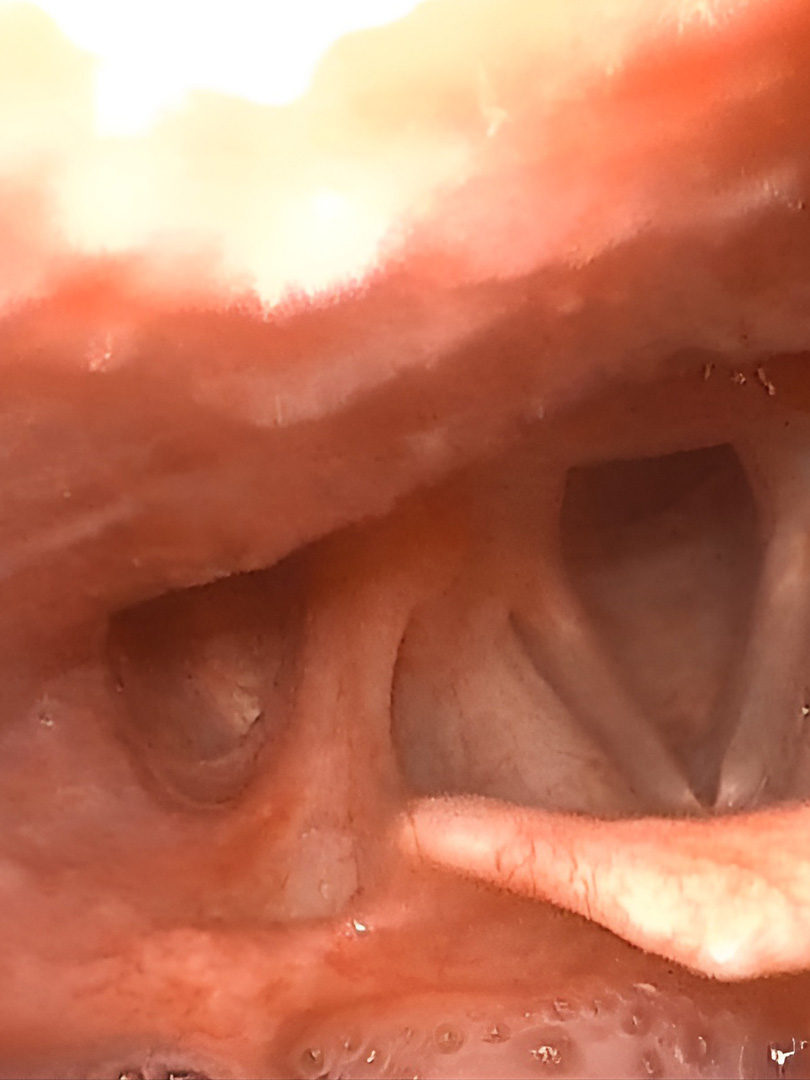

Estudio de Telelaringoscopia

Visualización detallada de la laringe en pantalla para evaluar la vibración de las cuerdas vocales y detectar lesiones para su diagnóstico y tratamiento.

Estudio de Nasofibrolaringoscopia

Evaluación dinámica e integral de toda la vía aérea superior mediante un fibroscopio flexible de alta precisión para determinar patologías complejas.